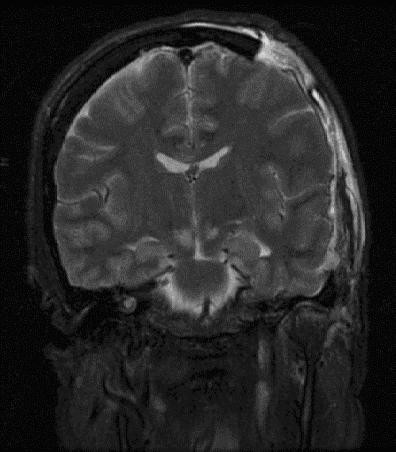

Brain herniation MRI.

Brain herniation.